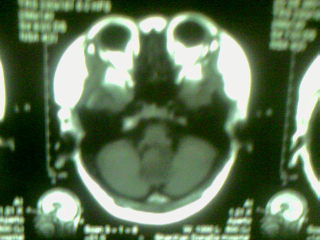

标题: MRI2125:女 45岁 头疼头晕3个月 [打印本页]

标题: MRI2125:女 45岁 头疼头晕3个月

1)考虑第四脑室脉络膜丛乳头状瘤,不排除室管膜瘤。2)阻塞性脑积水。

考虑 第四脑室室管膜瘤或脉络膜丛乳头状瘤伴梗阻性脑积水。

1)考虑第四脑室室管膜瘤,不排除脉络膜丛乳头状瘤。2)阻塞性脑积水。

第四脑室脉络丛乳头状瘤,典型!